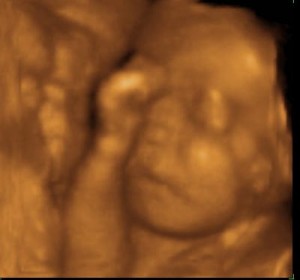

У крохи личико на вид такое, каким вы увидите его при рождении.

В матке малышу становится все теснее и теснее, теперь вы более отчетливее чувствуете его движения. Кроха свободно играется пуповиной, сосет свой пальчик, наклоняет голову, чтобы захватить губами пальчик, хмурит брови. Он все больше прислушивается к внешнему миру.